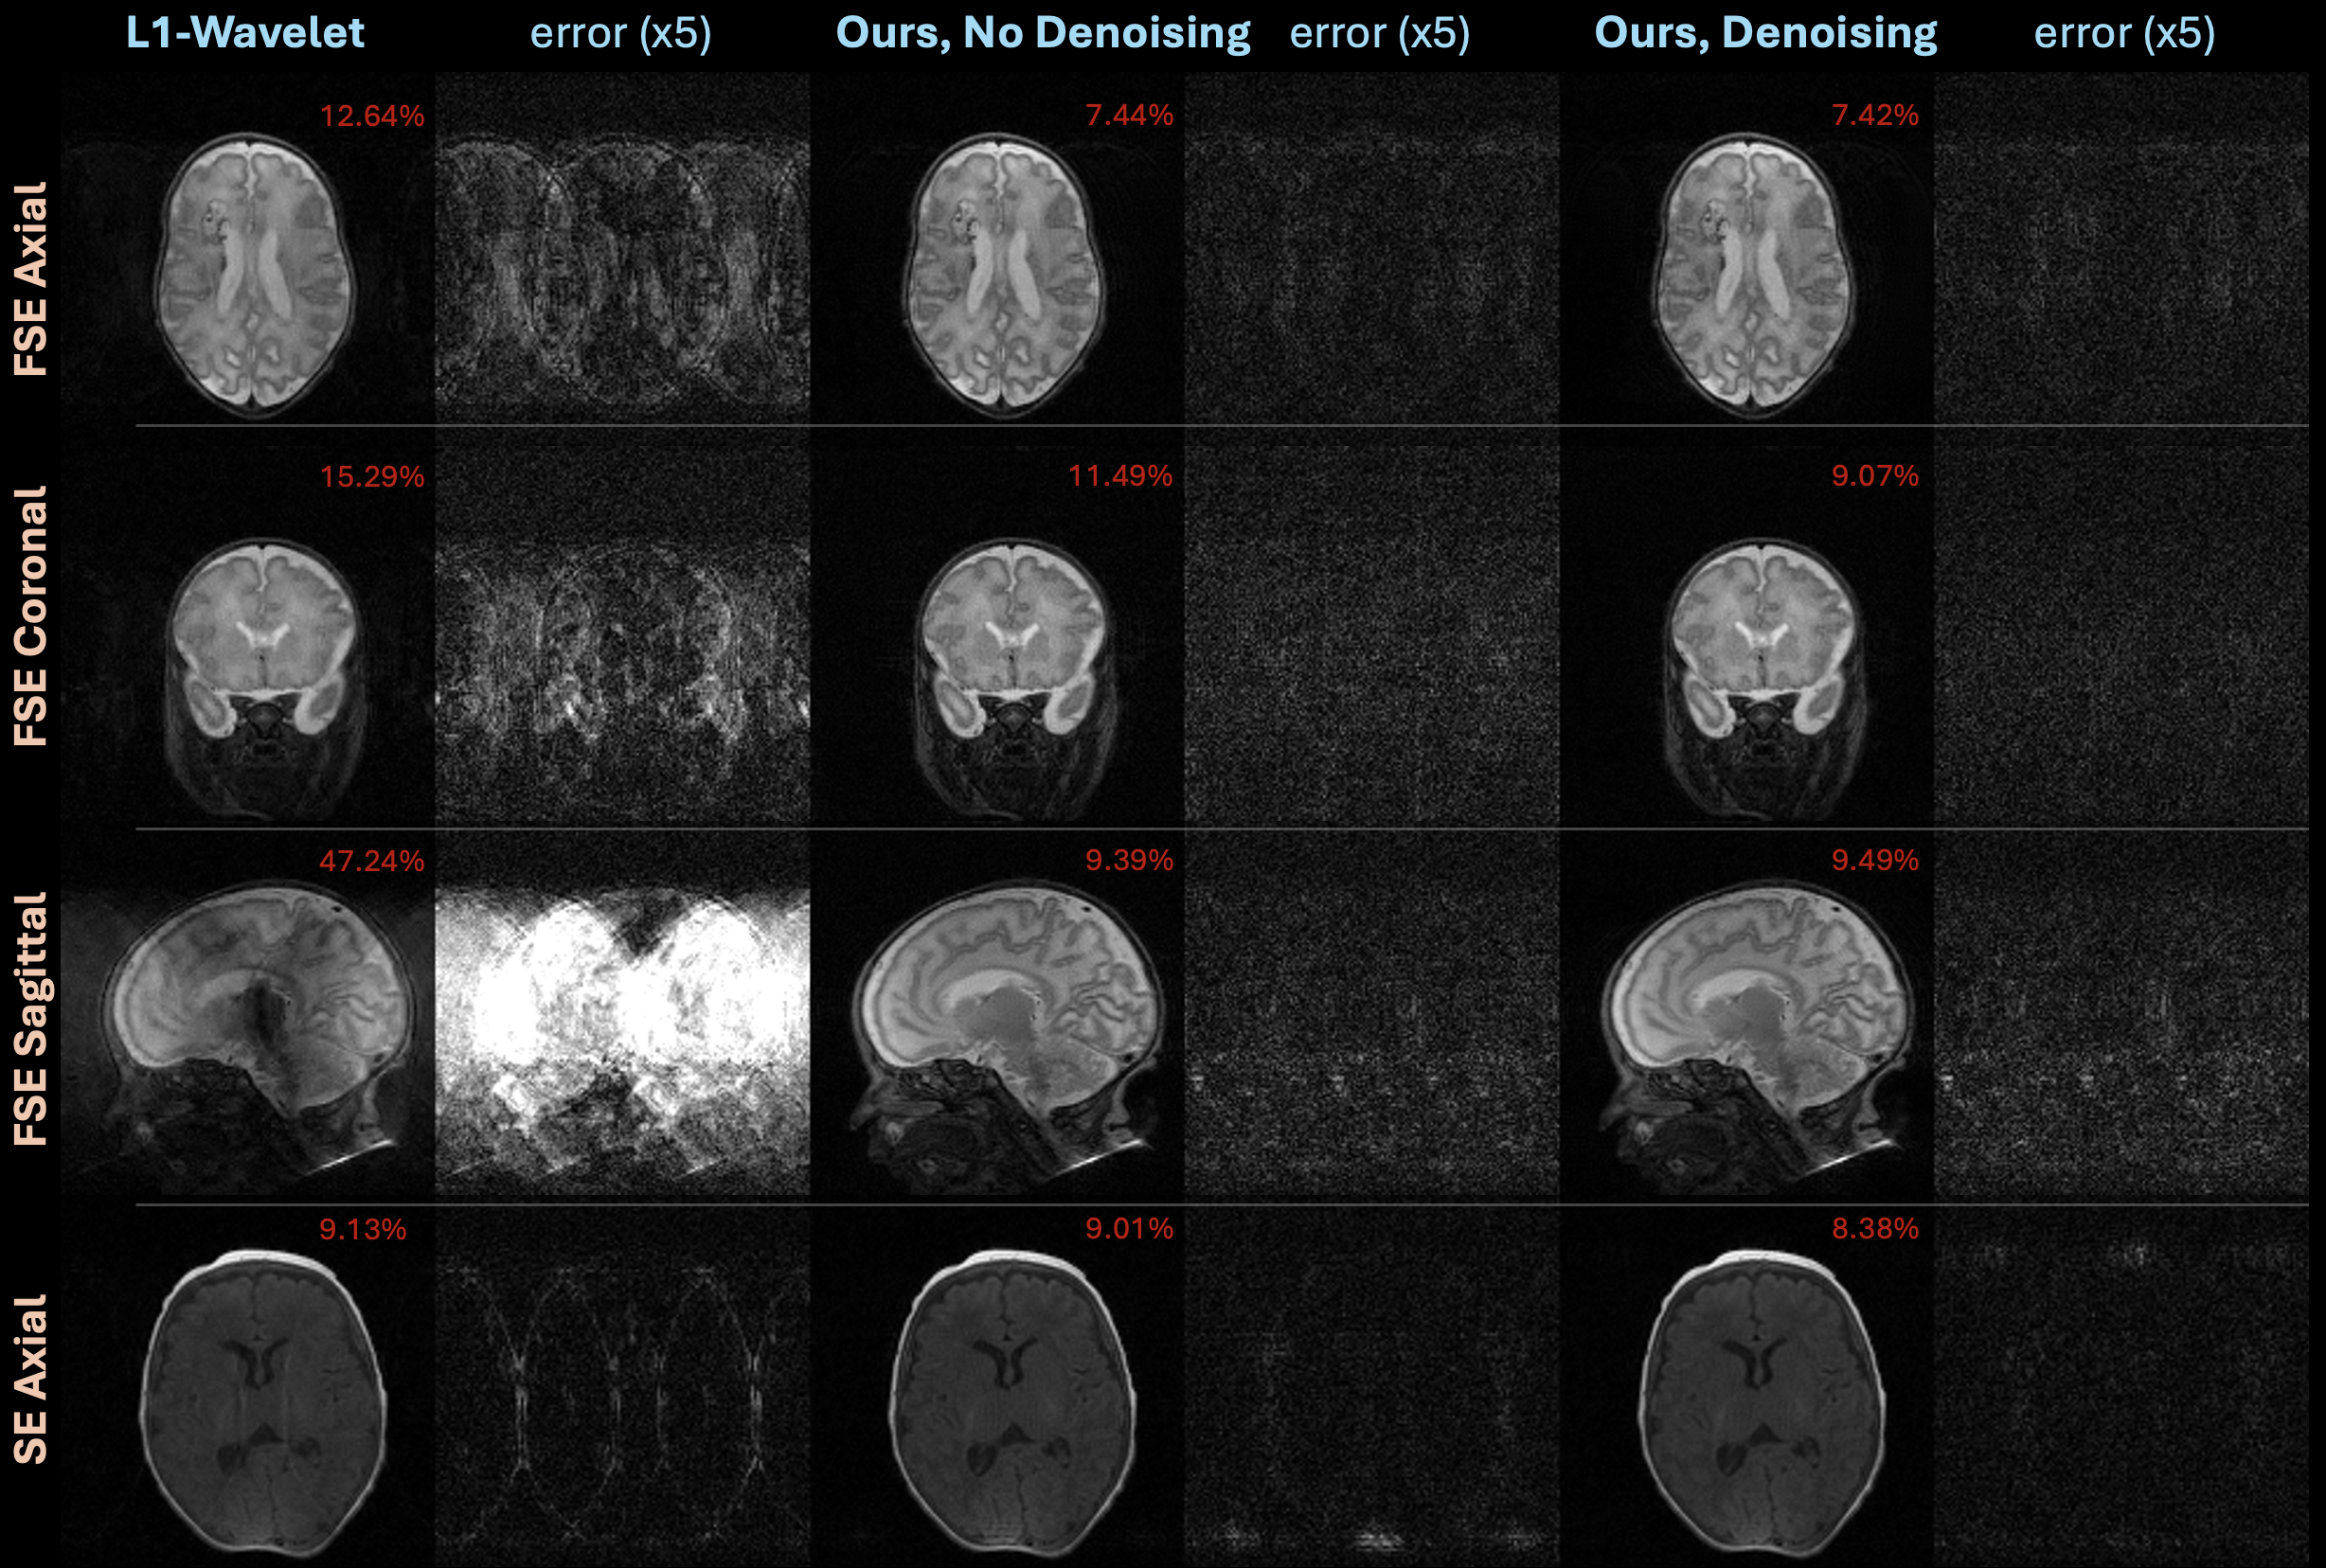

The violin plot in Figure 5 compares NRMSEs of reconstructions using non-learned L1-wavelet to generative models trained with class embeddings on all data with and without denoising. The non-learned method performs worse than both learned approaches, particularly on the FSE data. The difference in quantitative performance between models trained with and without denoising is small. Supporting Figure S3 shows example reconstructions from this experiment.

Figure 5: Violin plots comparing NRMSE of reconstructions on under-sampled data using baseline L1 and diffusion models trained on all data with and without denoising. While using a learned prior provides benefit, little quantitative difference exists between models trained with and without denoising pre-training.

Supporting Figure S3: Examples from the experiment comparing reconstructions on under-sampled data using an L1 baseline and diffusion models trained on all data with and without denoising. A learned prior provides benefit, but models with and without denoising do not exhibit clear differences in performance.